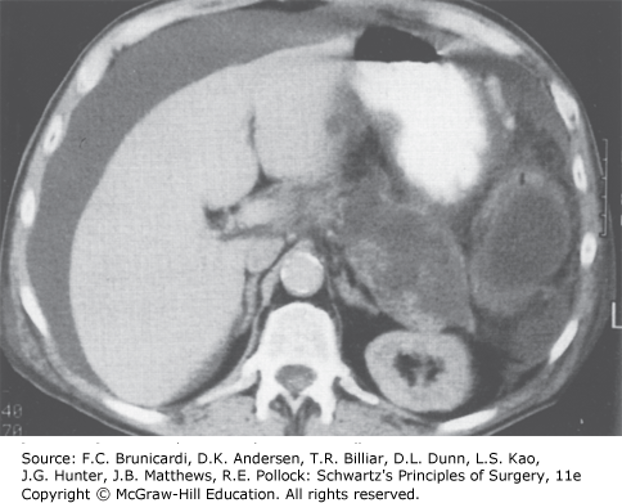

Pancreatic ascites. Computed tomographic scan of a patient with a ruptured pancreatic pseudocyst resulting in intraperitoneal pancreatic fluid. (Reproduced with permission from Cameron JL, Cameron AM: Current Surgical Therapy, 11th ed. Philadelphia, PA: Elsevier; 2014.)